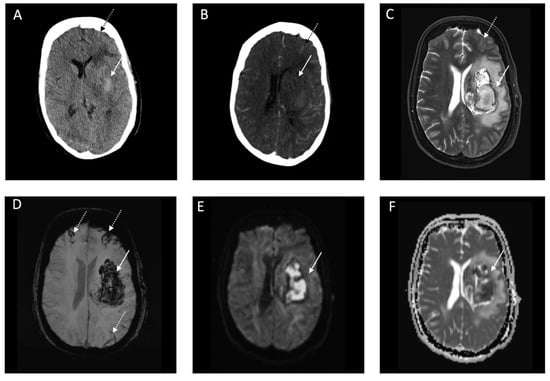

| Parenchymal Hemorrhage (n = 6) | |

| Location | |

| • Lobar, n (%) | 4 (66.7) |

| • Deep, n (%) | 1 (16.7) |

| • Infratentorial, n (%) | 1 (16.7) |

| Ventricular extension, n (%) | 1 (16.7) |

| SAH extension, n (%) | 1 (0) |

| Subarachnoid Hemorrhage (n = 11) | |

| Primary SAH, n (%) | 9 (81.8) |

| • Aneurysmal, n (%) | - |

| • Cortical, n (%) | 9 (81.8) |

| • Bilateral, n (%) | 4 (36.4) |

| • Ventricular extension, n (%) | - |

| Secondary SAH, n (%) | 2 (18.2) |

| Intraventricular Hemorrhage (n = 3) | |

| Isolated IVH | |

| • Supratentorial, n (%) | 3 (100) |

| • Infratentorial, n (%) | - |

| • SAH extension, n (%) | - |

| Secondary IVH *1, n (%) | 1 (33.3) |

| Subdural Hemorrhage (n = 1) | |

| Convexity, n (%) | 1 (100) |

| Bilateral, n (%) | - |

| SAH extension, n (%) | 1 (100) |